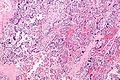

English: Very high magnification micrograph of maternal malaria. Placenta. H&E stain.

The images show organisms within the red blood cells. Related images

Red blood cell infected by malaria.

Red blood cell infected by malaria.